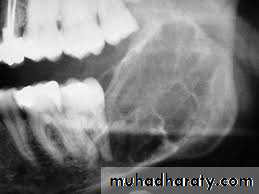

Raioraghical examination may demonstrate unlocular or multilocular types. Unilocular ameloblastomas may be confused with benign cysts. The tumors frequently absorbs the alveolus surrounding ,the roots of teeth and may absorb root ends.

Ameloblastoma grow by extension into adjacent tissues and may perforate the investing bone. A biopsy should precede treatment since

these tumors frequently present with individual characteristics.

Methods of treatment:

include extirpation, radical resection of the jaw. selective block excision and electro cauterization. Local excision of usually accessible tumor is indicated in the young.Provided, that they agree to regular follow - up and a radical resection when recurrence occurs. Recurrences are not unusual after curettage incomplete surgical treatment may stimulate tumor cell growth.